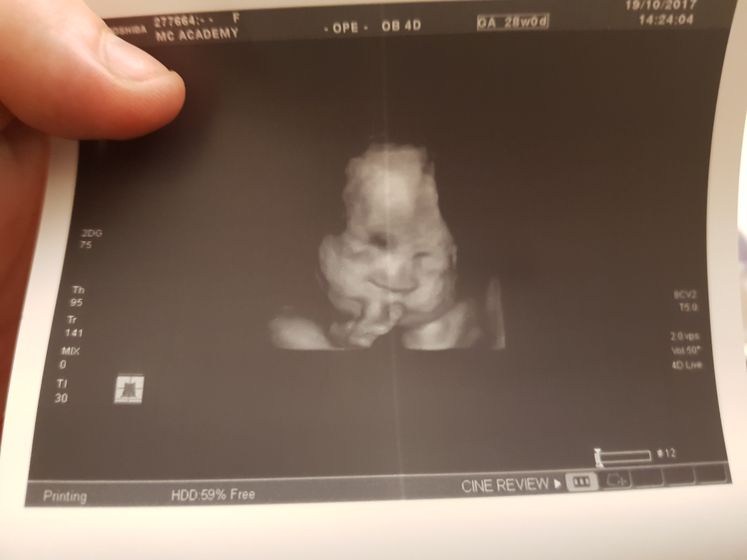

Сходила я сегодня на узи. Сидим на попке( все у нас в норме. Срок стоит 30-31 неделя, вот так вот) значит вдм соответствует узи)) весим мы 1418) и вот мы))

В академии, на стасово 18. Запись на флешку и фото на память) стоимость 1950

Так это 3д узи) оно на много качественее)